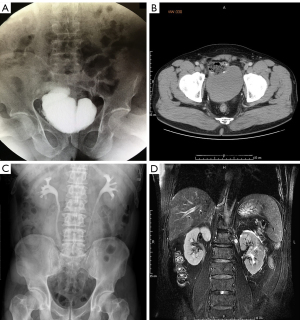

Perioperative data including median operative time, estimated blood loss, blood transfusion, number of lymph nodes removed, conversion to open surgery, and perioperative complications were assessed. Preoperative intravenous pyelogram (IVP) or computed tomography urography (CTU) examination was performed to assess the upper urinary tract tumor. All patients underwent preoperative computed tomography (CT) or magnetic resonance imaging (MRI) to assess tumor, lymph node status, and distant metastasis. The study was conducted in accordance with the Declaration of Helsinki (as revised in 2013). This study was approved by the Ethics Committee of the Third Medical Center of Chinese PLA General Hospital, Beijing, China (No. C2017-037-01). All patients signed written consent for permission to access their data for this study. All procedures were performed by surgeons with advanced robotic-assisted laparoscopic skills.

Patients was followed up every 3 months during the first year, every 6 months during the second year, and annually thereafter postoperatively. Physical examination, blood investigations including full blood count, and renal profile were performed during follow up. Chest X-ray, abdominal ultrasonography, and a CT or MRI scan were performed at postoperative 3 months, 6 months, and annually. Intravenous urography or renal ultrasonography was performed at 1, 3, and 6 months postoperatively to ensure patency of the anastomosis, and to rule out stricture or leakage. Additional imaging was performed as clinically indicated. Perioperative and postoperative outcomes were reported.

Patient characteristics are listed in Table 1. There were 23 males and 5 females with a mean age of 56.32 years and a mean body mass index (BMI) of 25.08 kg/m2. There was no conversion to open surgery and no perioperative mortalities. Totals of 22 males and 1 female were performed with intracorporeal orthotopic ileal neobladder; 1 male and 4 females were performed with intracorporeal ileal conduit. The mean operating time was 546 min (OIN) and 313 min (ICD). The median blood loss was 300 mL (IQR, 200–400 mL), with a transfusion rate of 17.86% (5 of 28). The median pelvic lymph node yield was 26 (range, 14–43). The average duration of bilateral UIA was about 40 min. All patients ambulated on postoperative 2 to 3 days, and bowel function recovered on either postoperative day 3 or 4. The median length of hospital stay was 14 days (IQR, 9–18 days). One month after operation, intravenous urography and renal ultrasonography were arranged to confirm patency of the ureteral ileal anastomosis. During the follow up of 6–76 months (median 29 months), all of the patients maintained normal renal functions and satisfactory urinary diversion without severe hydronephrosis (Table 2).

No urine leakage or stricture were observed for patients who underwent “V-O manner” UIA in postoperative imaging. No patient was complicated with stoma hernia. Creatinine level for all participants remained stable during the follow up period for at least 6 months (Figure 2).